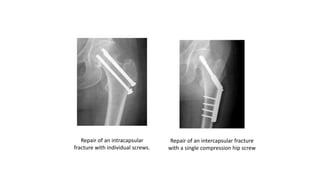

1. Intracapsular Fracture:

o For true intracapsular hip fractures, the surgeon may decide either to fix the

fracture with individual screws (percutaneous pinning) or a single larger

screw that slides within the barrel of a plate. This compression hip screw will

allow the fracture to become more stable by having the broken area impact

on itself. Occasionally, a secondary screw may be added for stability.

Repair of an intracapsular

fracture with individual screws.

Repair of an intercapsular fracture

with a single compression hip screw